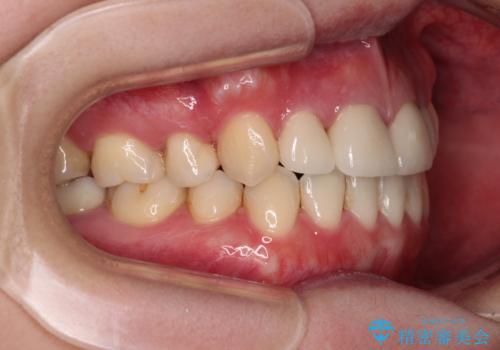

- 八重歯と前歯のデコボコ、開咬を気にして来院された患者様です。

抜歯矯正が必要であることはご自身で理解されており、目立たない装置をご希望であったので、上顎が裏側装置であるハーフリンガル装置にて治療を行うこととしました。